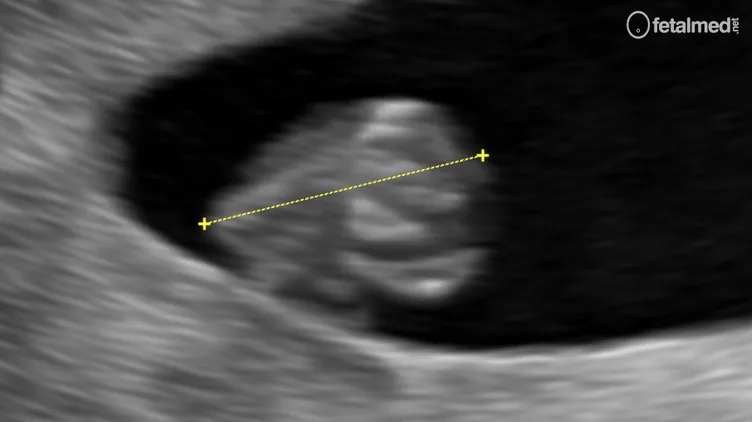

Medida do comprimento cabeça-nádegas CCN ao ultrassom transvaginal no primeiro trimestre da gestação

Imagem de ultrassom demonstrando a medida do comprimento cabeça-nádegas (CCN) no primeiro trimestre. Os calipers estão posicionados do polo cefálico ao polo caudal do embrião.

A medida do CCN deve ser realizada no maior eixo longitudinal do embrião/feto, do polo cefálico ao polo caudal. Nos estágios iniciais da gestação (antes de 8 semanas), o embrião pode ser identificado pelo batimento cardíaco. A partir de 7 semanas, os polos cefálico e caudal tornam-se distinguíveis, permitindo uma medida mais precisa.